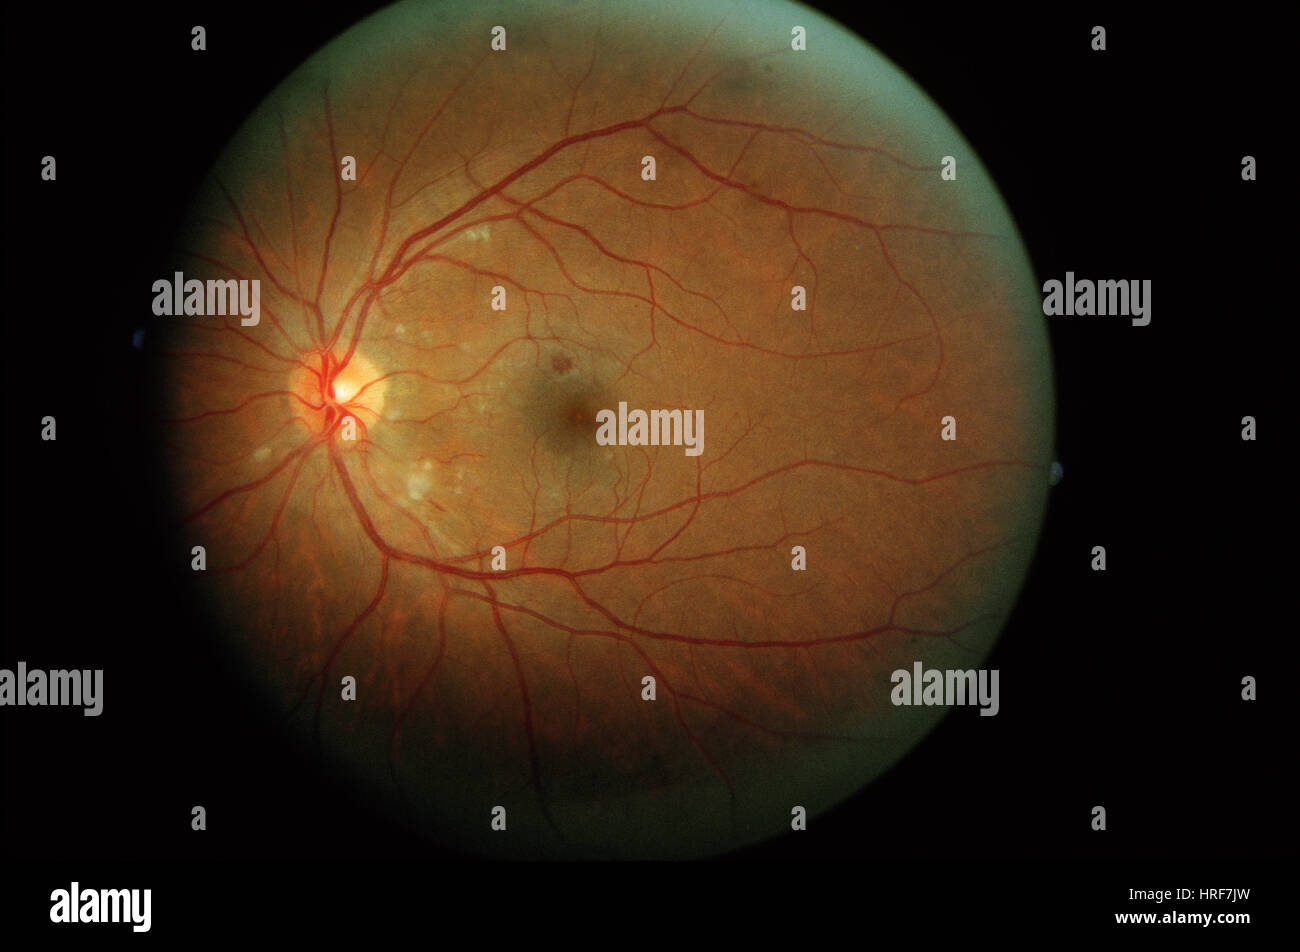

Diabetic Retinopathy Stock Photohttps://www.alamy.com/image-license-details/?v=1https://www.alamy.com/stock-photo-diabetic-retinopathy-134944962.html

Diabetic Retinopathy Stock Photohttps://www.alamy.com/image-license-details/?v=1https://www.alamy.com/stock-photo-diabetic-retinopathy-134944962.htmlRMHRF7JX–Diabetic Retinopathy